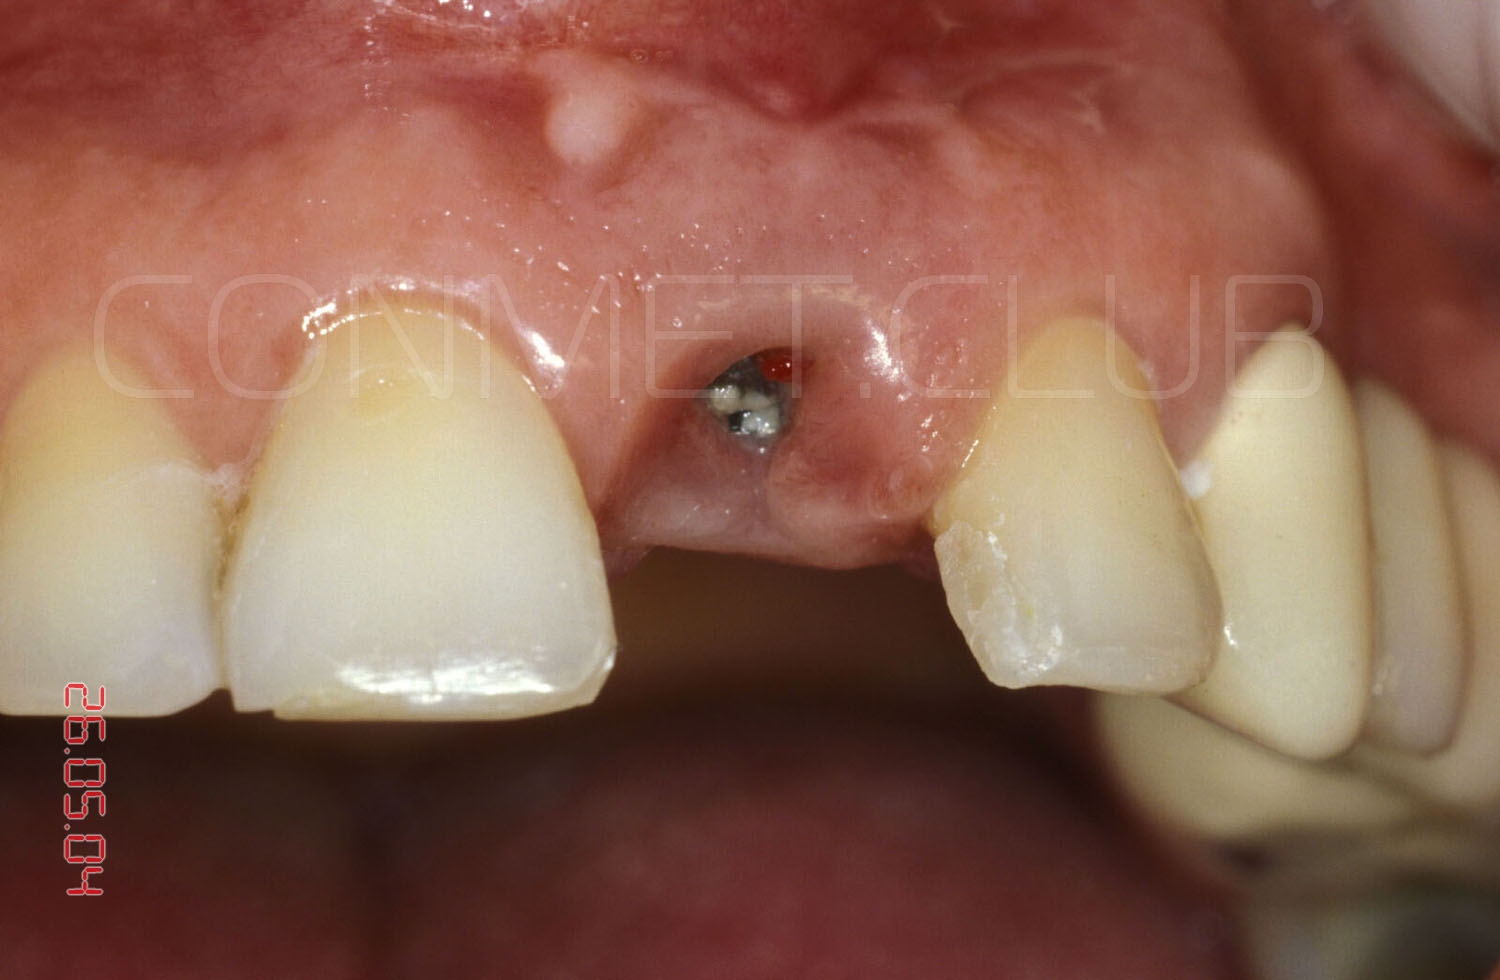

Для людей сомневающихся в правдивости и сроках - предлагаем два снимка из этой серии с оригинальными штампами даты

немедленная имплантация с использованием имплантата КОНМЕТ (полированная трансгингивальная часть, пескоструйная обработка эндооссальной части) с неполной облитерацией лунки удаленного зуба; интерфейс имплантата-только конус Морзе без антиратационных элементов внутри; глубокое резцовое перекрытие. Результат: 15 лет функционирования без единой проблемы с имплантатом и коронкой (ни малейшей ротации и ни единой расцементировки), идеальное, для такой ситуации сохранение межзубных сосочков.